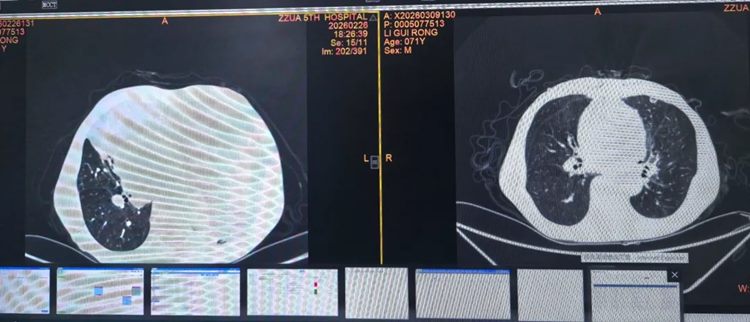

▲ 术前(左侧)与术后(右侧)肺窗对比